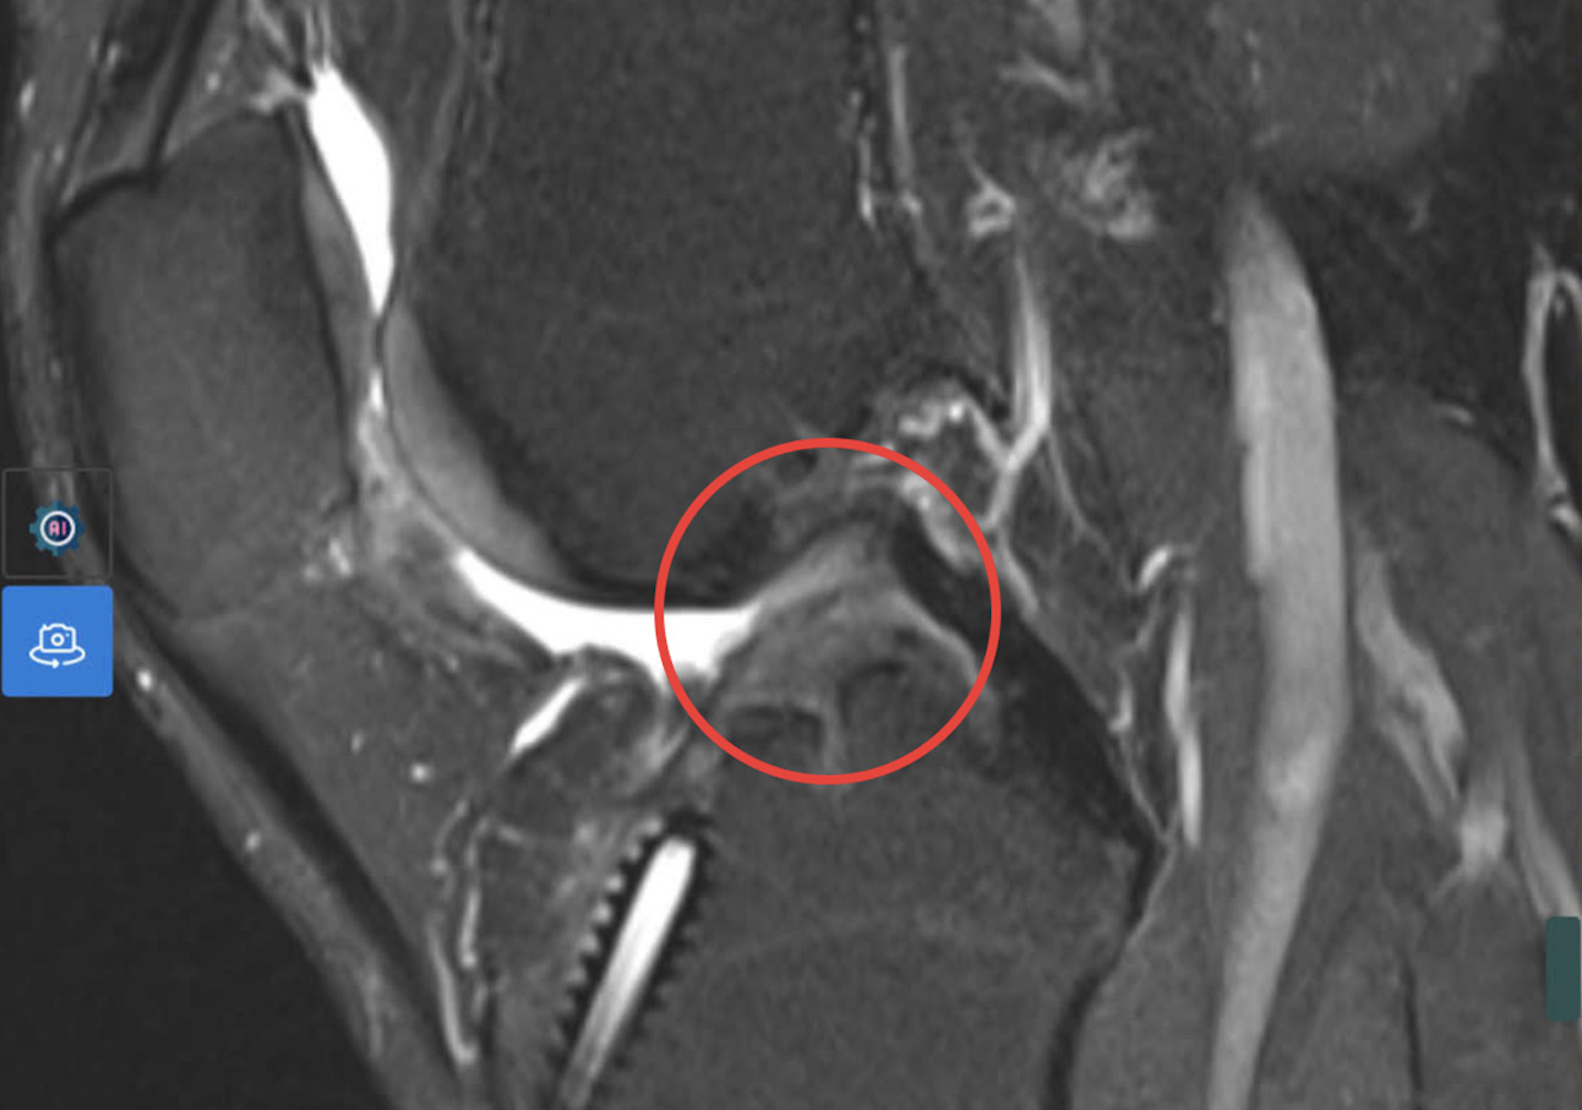

MRI results showed a complete anterior cruciate ligament tear. Photo: Tam Anh General Hospital.

Doctors conducted MRI and CT scans to reconstruct the knee joint. This allowed them to examine the existing tunnel and surrounding structures, guiding the selection of the tendon graft, fixation devices, and precise tunnel placement. The procedure began with an arthroscopy to directly assess intra-articular damage. Previous ligament fixation devices were removed, the area was cleaned, and a new tunnel was created using CT guidance. Subsequently, a segment of the superficial quadriceps tendon was harvested from the front of the thigh, above the patella, to form the ligament graft based on precise measurements.